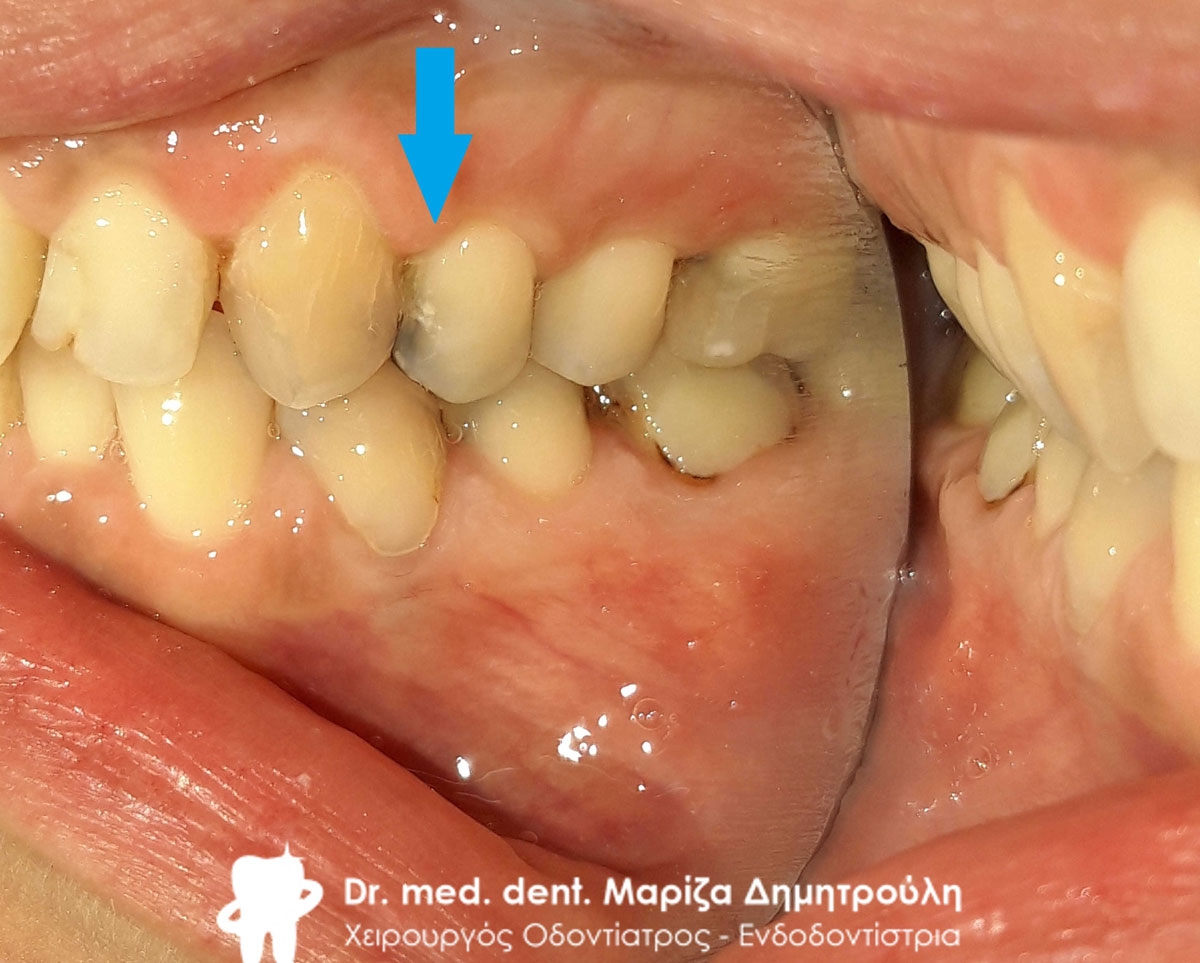

Αρχική κλινική εικόνα της αριστερής πλευράς της κάτω γνάθου

Αρχική κλινική εικόνα της αριστερής πλευράς της κάτω γνάθου

Αρχική κλινική εικόνα της αριστερής πλευράς της κάτω γνάθου